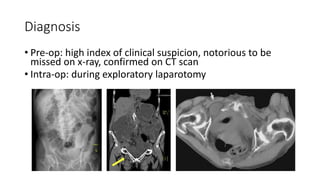

Diagnosis

• Pre-op: high index of clinical suspicion, notorious to be

missed on x-ray, confirmed on CT scan

• Intra-op: during exploratory laparotomy

Diagnosis • Pre-op: highindex of clinical suspicion, notorious to be missed on x-ray, confirmed on CT scan • Intra-op: during exploratory laparotomy